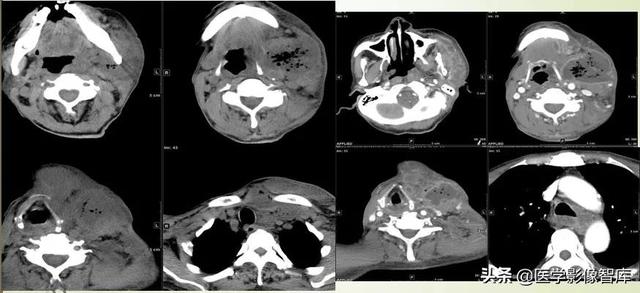

多间隙受累

(1)左下后牙疼痛11天余,颈部肿胀10天。

(2)右侧颌面部弥漫性肿胀1月余。